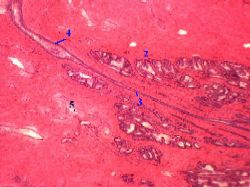

II. Мышечно-эластическая строма простаты

| 3,д-е. Препарат - предстательная железа собаки. Окраска гематоксилин- эозином. | (Малое увеличение) д)Полный размер | (Большое увеличение) е)Полный размер |

1. Как следует из названия стромы, в ней - два основных компонента: пучки гладких миоцитов (2) и рыхлая волокнистая соединительная ткань (5) с большим содержанием эластических волокон. 2. а) Мышечные пучки окружают дольки и в них отдельные концевые отделы двумя слоями – циркулярным и продольным. б) Кроме того, они окружают уретру(образуя её мышечную оболочку) - и тоже двумя слоями: внутренним продольным и наружным циркулярным.. |